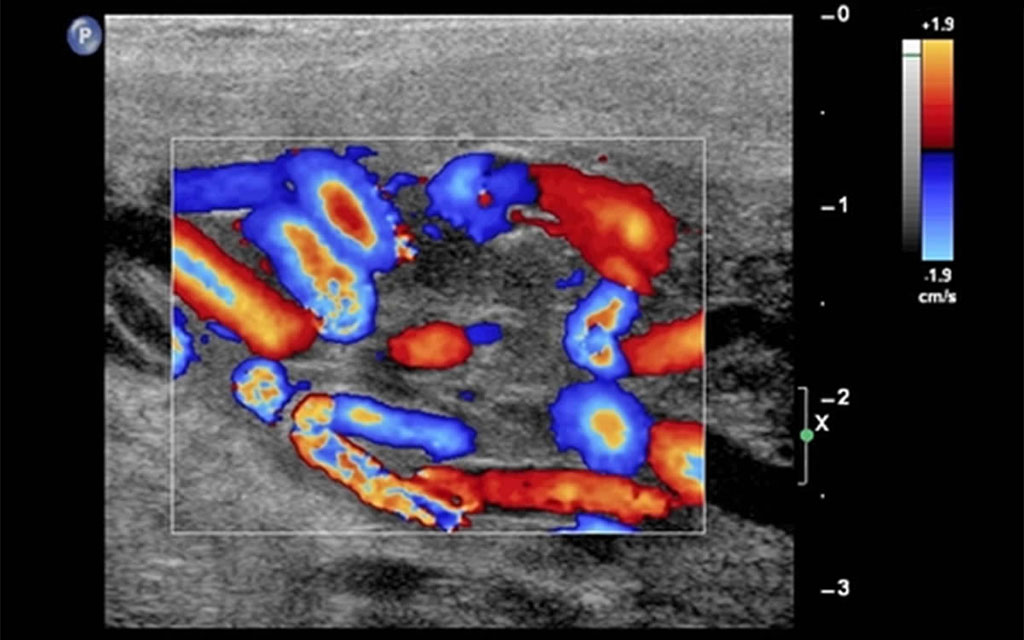

L’esame consiste nel movimento della sonda ecografica sulle borse scrotali (e regioni limitrofe) al fine della corretta visione di tutto l’apparato genitale, specificatamente del funicolo spermatico e dei testicoli, di cui è possibile eseguire una veduta volumetrica e morfologica.

L’ecografia testicolare utilizza gli ultrasuoni – onde sonore ad alta frequenza non percepibili dall’orecchio umano – che attraversano le componenti dell’apparato genitale, che le riflettono in base alla diversa composizione (densità). Questo permette all’ecografo di generare l’immagine diagnostica visualizzata sullo schermo.